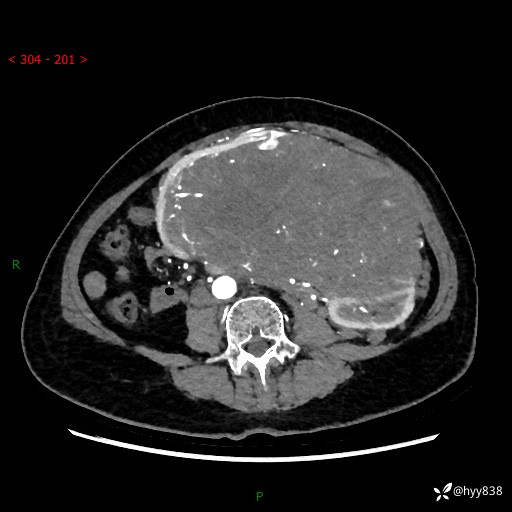

据说只有腹膜后,才能见到如此巨大的肿块---(有结果)

主诉:发现腹膜后占位1周

简要病史:患者1周前因头晕在当地第二人民医院检查发现左侧腹膜后区巨大富血供占位性病变,患者自诉腹部稍硬,无其他不适,无血尿,无腰痛等不适,患者为求进一步治疗来我院,门诊以“腹膜后占位性病变”收入我科。 起病以来,患者精神、饮食、睡眠可,大便正常,小便如上述,体力体重无明显改变。

临床诊断:腹膜后占位

腹部CT增强(动脉期+静脉期 ) ---平扫外院